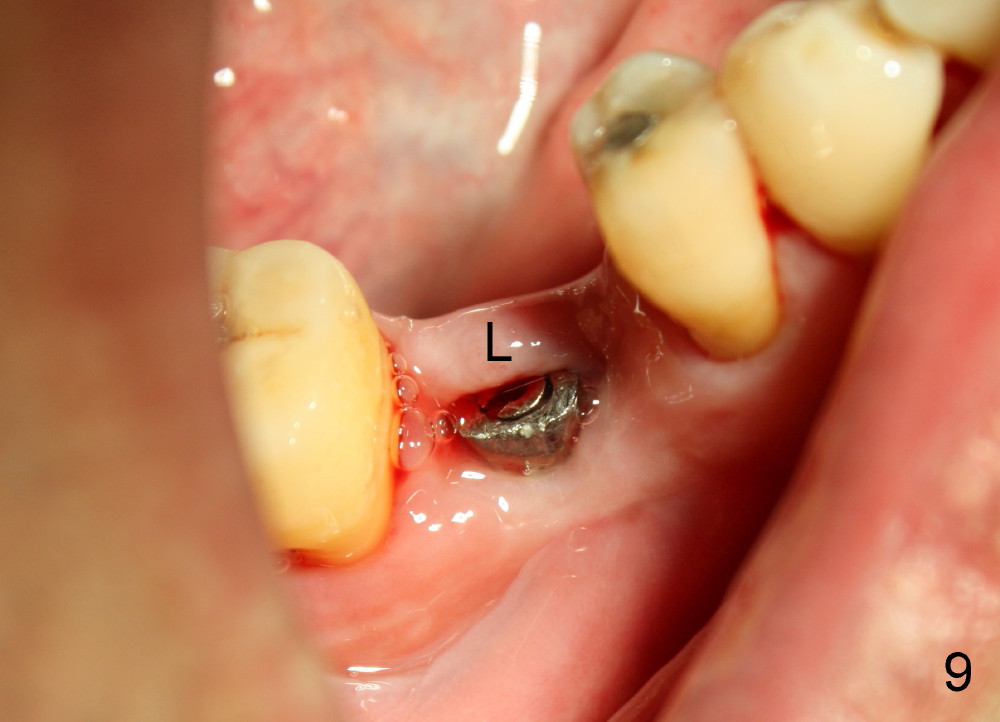

A 46-year-old man has severe periodontitis. The tooth #30 is complicated by incomplete root canal therapy (Fig.1,2). Three months after extraction (Fig.3-5: N: inferior alveolar canal), a 5x14 Tatum tapered implant is placed (Fig.6,7). The problem is that an implant driver is fractured (D in Fig.7), while the implant is being torqued. It takes time and effort to remove the fractured driver, but the implant is solid. The healing screw is placed without difficulty (Fig.8). Since the implant is placed lower than the lingual gingiva (L in Fig.9), a healing cuff is placed 1.5 months after implant placement (Fig. 10 and 11: C) to push the lingual gingiva down. The X-ray appears to show lower bone density around the implant (bone necrosis?), although the implant has no mobility at all. Since the implant is so solid, can we load it, two months after surgery? The lingual gingiva is now lower than the healing cuff (not shown). CT is scheduled to be taken tomorrow. Thanks.